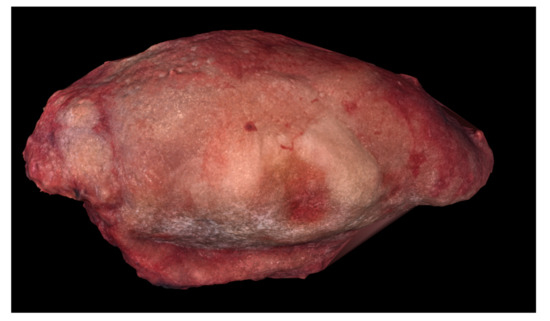

Digital 3D model of Case 2 using Meshlab.

Figure 6.